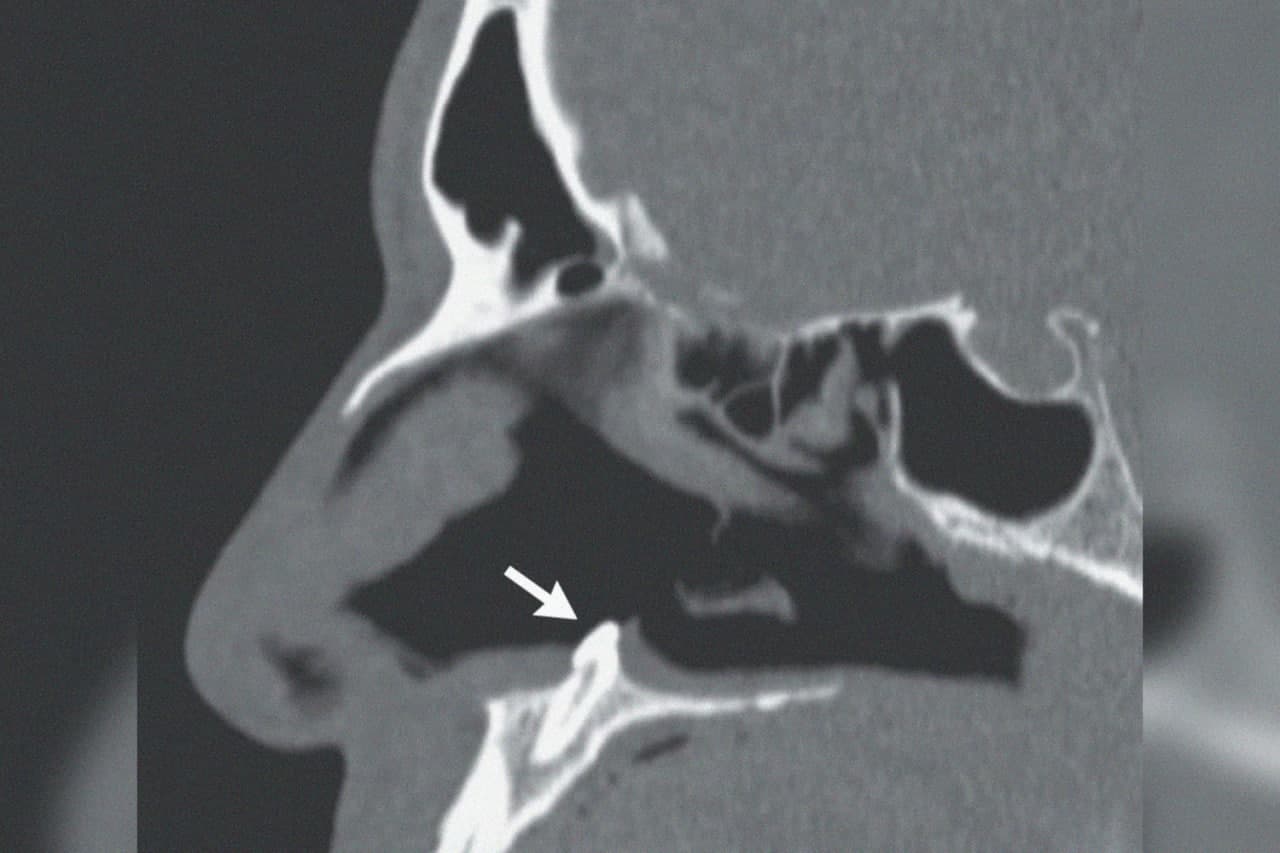

Мужчина обратился в больницу с жалобами на затрудненное дыхание, которое мучило его уже несколько лет. На осмотре врачи обнаружили искривление перегородки, а также неясное уплотнение в глубине ноздри. Компьютерная томография показала, что это эктопический (выросший в неположенном месте) зуб.